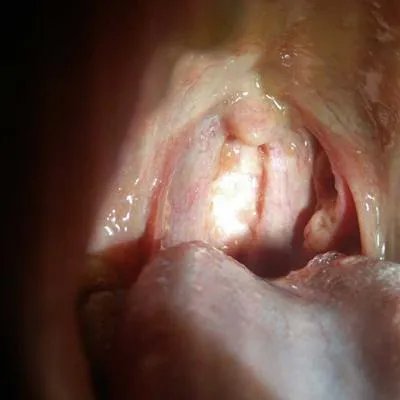

第一:引起舌头开裂,主要的原因就是因为口腔卫生的不干净造成的,很多的人不经常刷牙,这会就会造成口腔内有很多的细菌,从而就会导致舌头开裂的疾病,也有一些原因是先天性的舌头开裂,

第三:随着年龄的增长,对于这个疾病的发病率也是逐渐升高的,我们大家都应该知道这个石头,它是具有很多种复杂结构的,一般来说,症状比较轻点的话是不需要治疗的,如果症状比较严重的话,我们可以采用一些维生素b或者是,2%的碳酸氢钠液漱口,